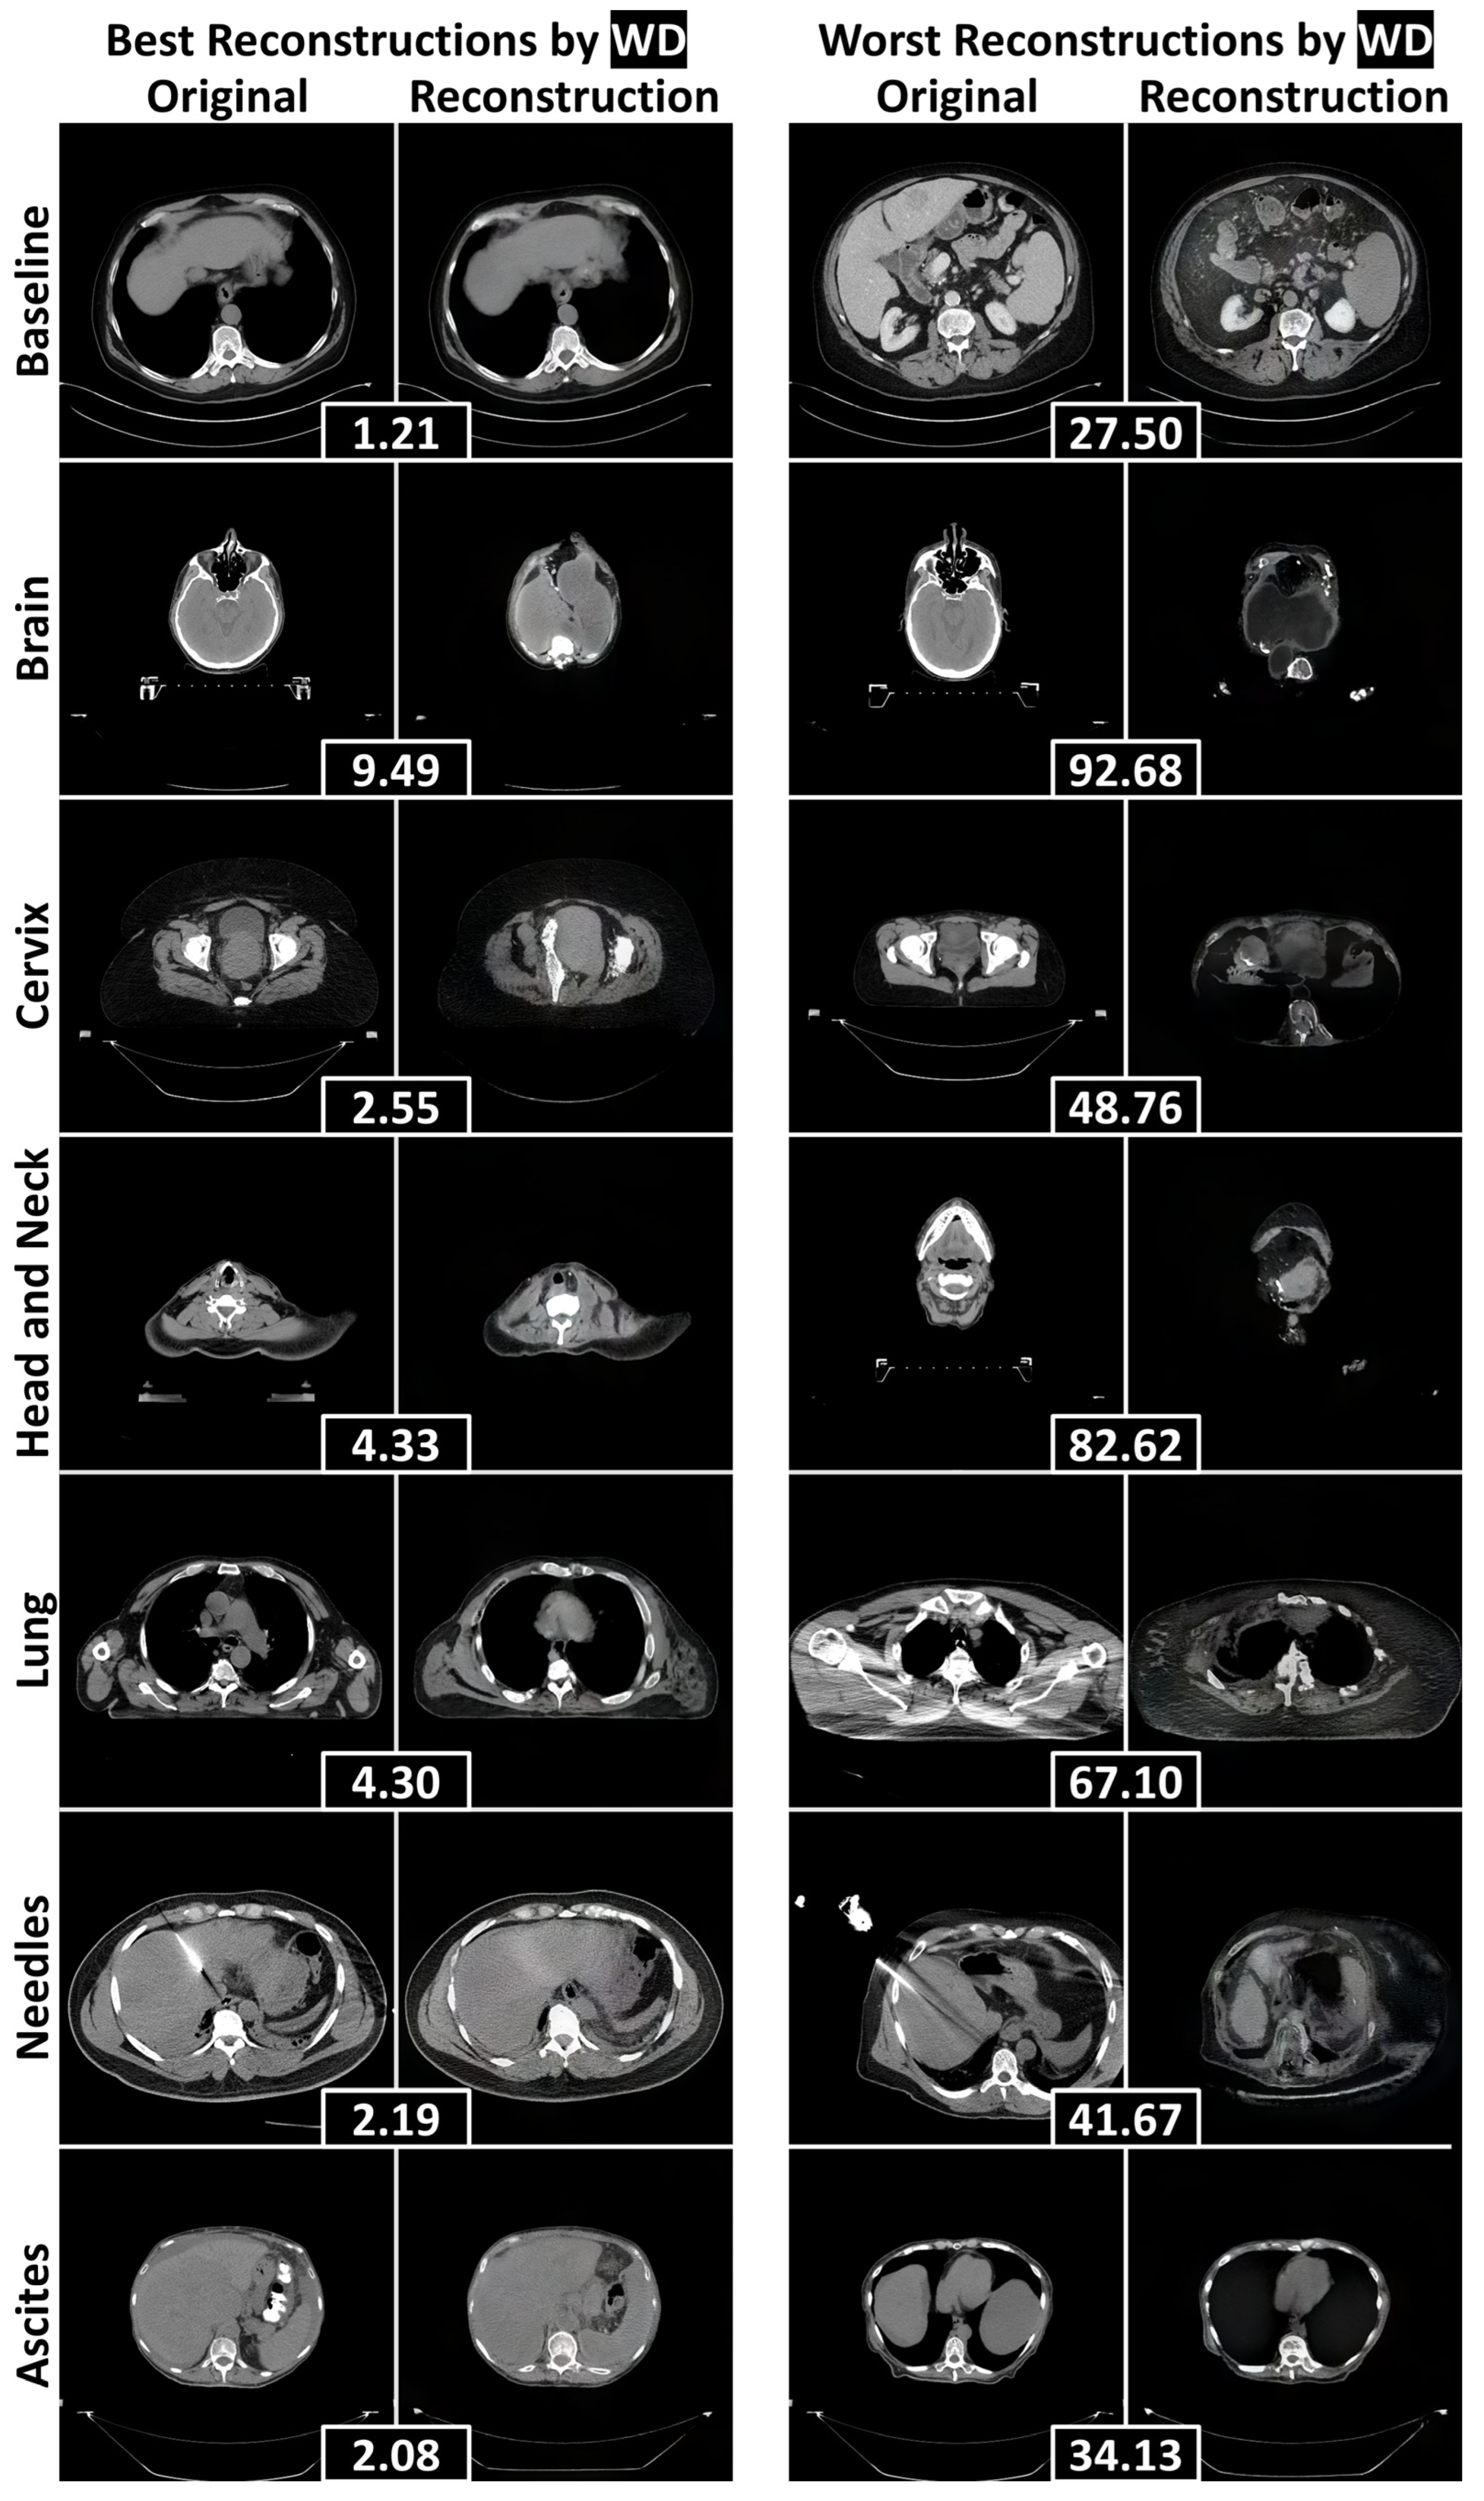

3.2. Reconstruction Performance and Interpretation

3.3. Quantitative Anomaly Detection Performance